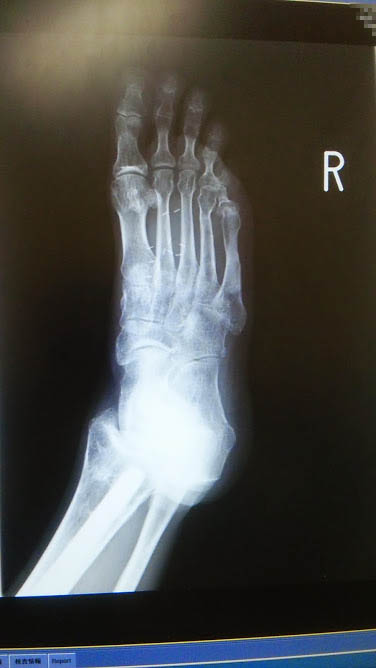

恒例の写真撮影をお願いしたら

前と同じように撮らせてもらいました

今悩みの種

甲の骨が反っているので

素足で歩くのが厳しい状態

今まで当たらなかった靴が当たる

小指と同じ現象に

小指の骨がガタガタです

何度かOPEしたせい

しばらく温存治療などしつつ経過観察